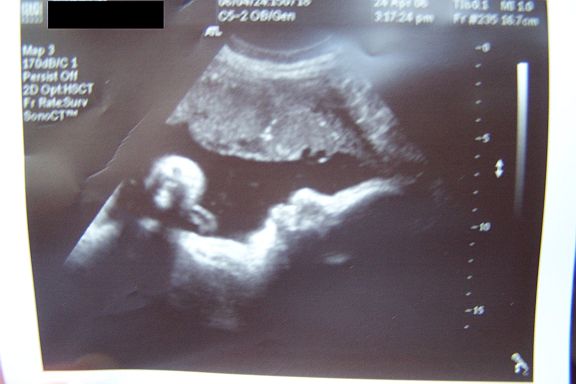

Hopefully I'll know by tomorrow or Wednesday. Oh and I have another sono pic from today even though its not the greatest since she is so big. I'll try to post it.

ETA: here's the sono pic. Sorry I didnt scan it, just took a pic of it with my camera so its not the best quality. Image Attachment(s):